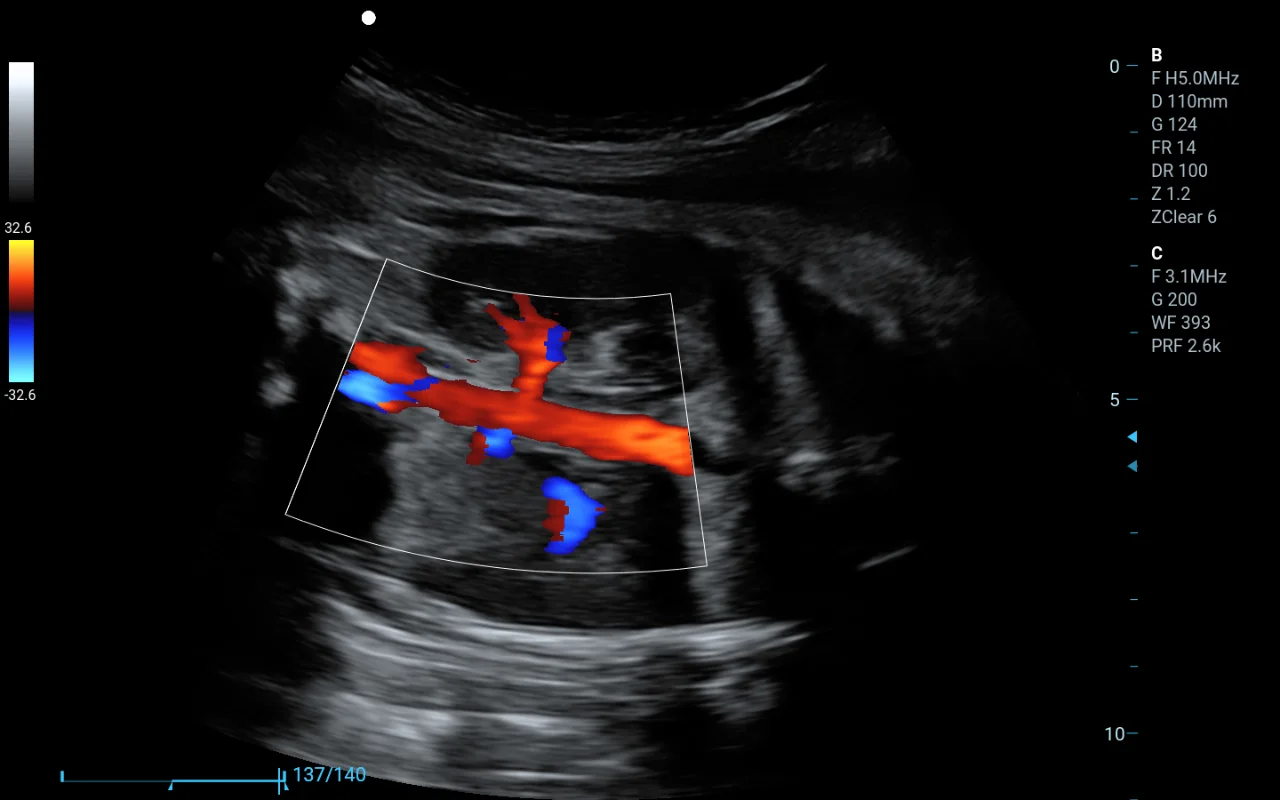

三維醫(yī)學(xué)影像軟件屬于哪類醫(yī)療器械?

王姐是一家醫(yī)療軟件公司的負(fù)責(zé)人,最近她的團(tuán)隊(duì)開(kāi)發(fā)了一款三維醫(yī)學(xué)影像軟件,能將CT、MRI等醫(yī)學(xué)影像數(shù)據(jù)轉(zhuǎn)化為三維立體圖像,方便醫(yī)生進(jìn)行診斷。但是她不知道這款軟件屬于幾類醫(yī)療器械?需要怎么注冊(cè)備案?

三維醫(yī)學(xué)影像軟件屬于第二類醫(yī)療器械

醫(yī)療軟件根據(jù)功能和用途不同,可能屬于第一類、第二類或第三類醫(yī)療器械。她們的三維醫(yī)學(xué)影像軟件雖然可以對(duì)醫(yī)學(xué)影像進(jìn)行三維重建,但并不具備自動(dòng)診斷功能,僅作為醫(yī)生診斷的輔助工具。因此,它被歸為第二類醫(yī)療器械。

三維掃描儀器.jpg

在醫(yī)院醫(yī)生可以利用這類軟件查看病人的CT或MRI影像,通過(guò)三維重建的圖像更直觀地判斷病變部位,這相當(dāng)于給醫(yī)生提供了一雙“立體眼睛”,但最終的診斷還是由醫(yī)生來(lái)完成。這就是為什么它屬于第二類,而不是更嚴(yán)格的第三類醫(yī)療器械。